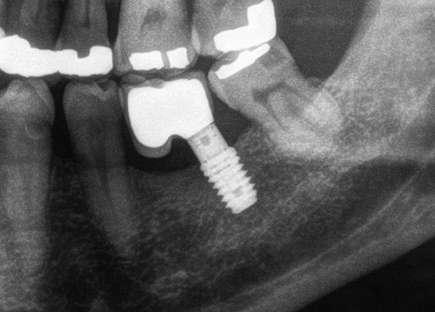

Figuras 3-6. Imágenes de un caso de prótesis atornillada en molar unitario inferior. Vemos el estado de los tejidos blandos gingivales tras la segunda fase y colocación del transepitelial unitario y la radiografía. En las imágenes inferiores (5 y 6) observamos el caso a los 4 años y 10 años de seguimiento, con estabilidad completa de los tejidos óseos peri-implantarios.

Figuras 7-10. En las dos imágenes superiores (7 y 8) observamos la realización de la prótesis cementada mediante un bioplilar fresado a la altura gingival con la radiografía antes del cementado de la corona. En las imágenes inferiores (9 y 10) vemos la prótesis a los 7 años de seguimiento y a los 9 años transformada en una prótesis atornillada al perderse la pieza anterior al implante y realizarse un puente con el nuevo implante. En este caso, el nivel óseo permanece estable con el paso del tiempo.